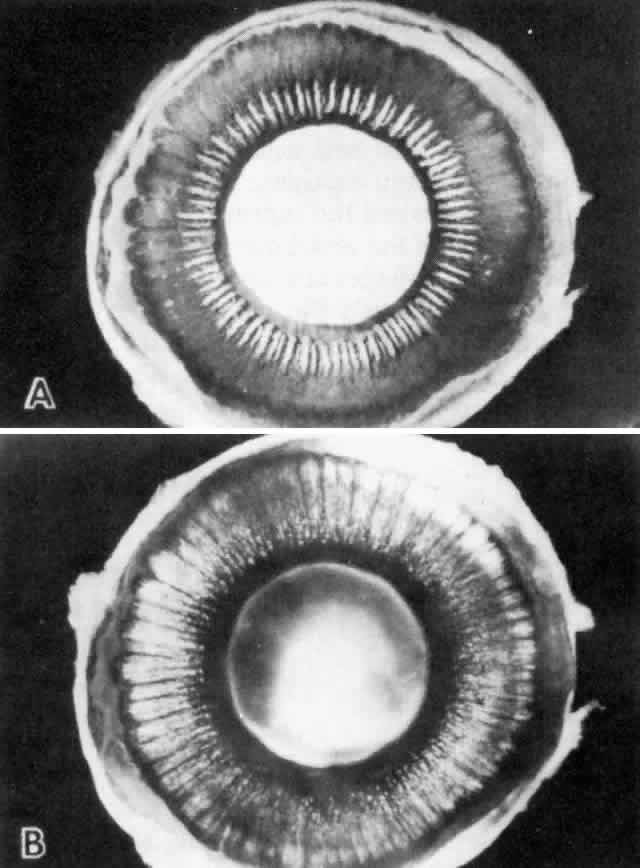

in number, and the cells become slightly smaller (Fig. 12). In the pars plicata the NPE cells are cuboidal, 12 to 15 μm in width, with

of these two layers (Fig. 14).  Fig. 12. Frontal view of a ciliary process at its junction with iris, showing conversion

to thicker, double-layered iris pigment epithelium (arrows). (Toluidine

blue, X 200) Fig. 12. Frontal view of a ciliary process at its junction with iris, showing conversion

to thicker, double-layered iris pigment epithelium (arrows). (Toluidine

Fig. 13. Ciliary nonpigmented epithelium. A. Anterior pars plicata, age 3. (hematoxylin-eosin, X 800) B. Posterior pars plicata with areas of thickened, pigmented

epithelium, age 3. m, ciliary muscle (hematoxylin-eosin, X 800) C. Nodular

proliferation of the nonpigmented epithelium appears

as small cellular caps over the surface at age 70. Z, zonule. (hematoxylin-eosin, X 400) D. Distorted epithelium of pars plana shows evidence

of traction in both anterior and posterior directions (adult). (hematoxylin-eosin, X 400) Fig. 13. Ciliary nonpigmented epithelium. A. Anterior pars plicata, age 3. (hematoxylin-eosin, X 800) B. Posterior pars plicata with areas of thickened, pigmented

epithelium, age 3. m, ciliary muscle (hematoxylin-eosin, X 800) C. Nodular

proliferation of the nonpigmented epithelium appears

as small cellular caps over the surface at age 70. Z, zonule. (hematoxylin-eosin, X 400) D. Distorted epithelium of pars plana shows evidence

of traction in both anterior and posterior directions (adult). (hematoxylin-eosin, X 400)